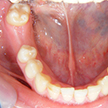

7. 施術前下顎観

下顎も1歯レベルでは本当に良い歯質をしています。残念なのは右下6番部の欠損(残根は抜歯済み)と、左下に存在する埋伏の5番と6番の関係です。やはり小児期の咬合誘導や口腔保健の対応は重要です。ただ子供の歯の虫歯だけ詰めるのが小児歯科ではありません。(6番は再根治して保健にて冠装着済み)問題は右下で、両隣の天然歯を削ってブリッジにするかどうかです。

8. 施術前右側観

6番部の欠損です。両隣在歯は良い歯をしています。絶対削りたくありません。ましてやブリッジにするために、最後臼歯の咬頭関係を崩してまで削るのは、咬合を崩すことになります。単独インプラント適応です。22歳です。